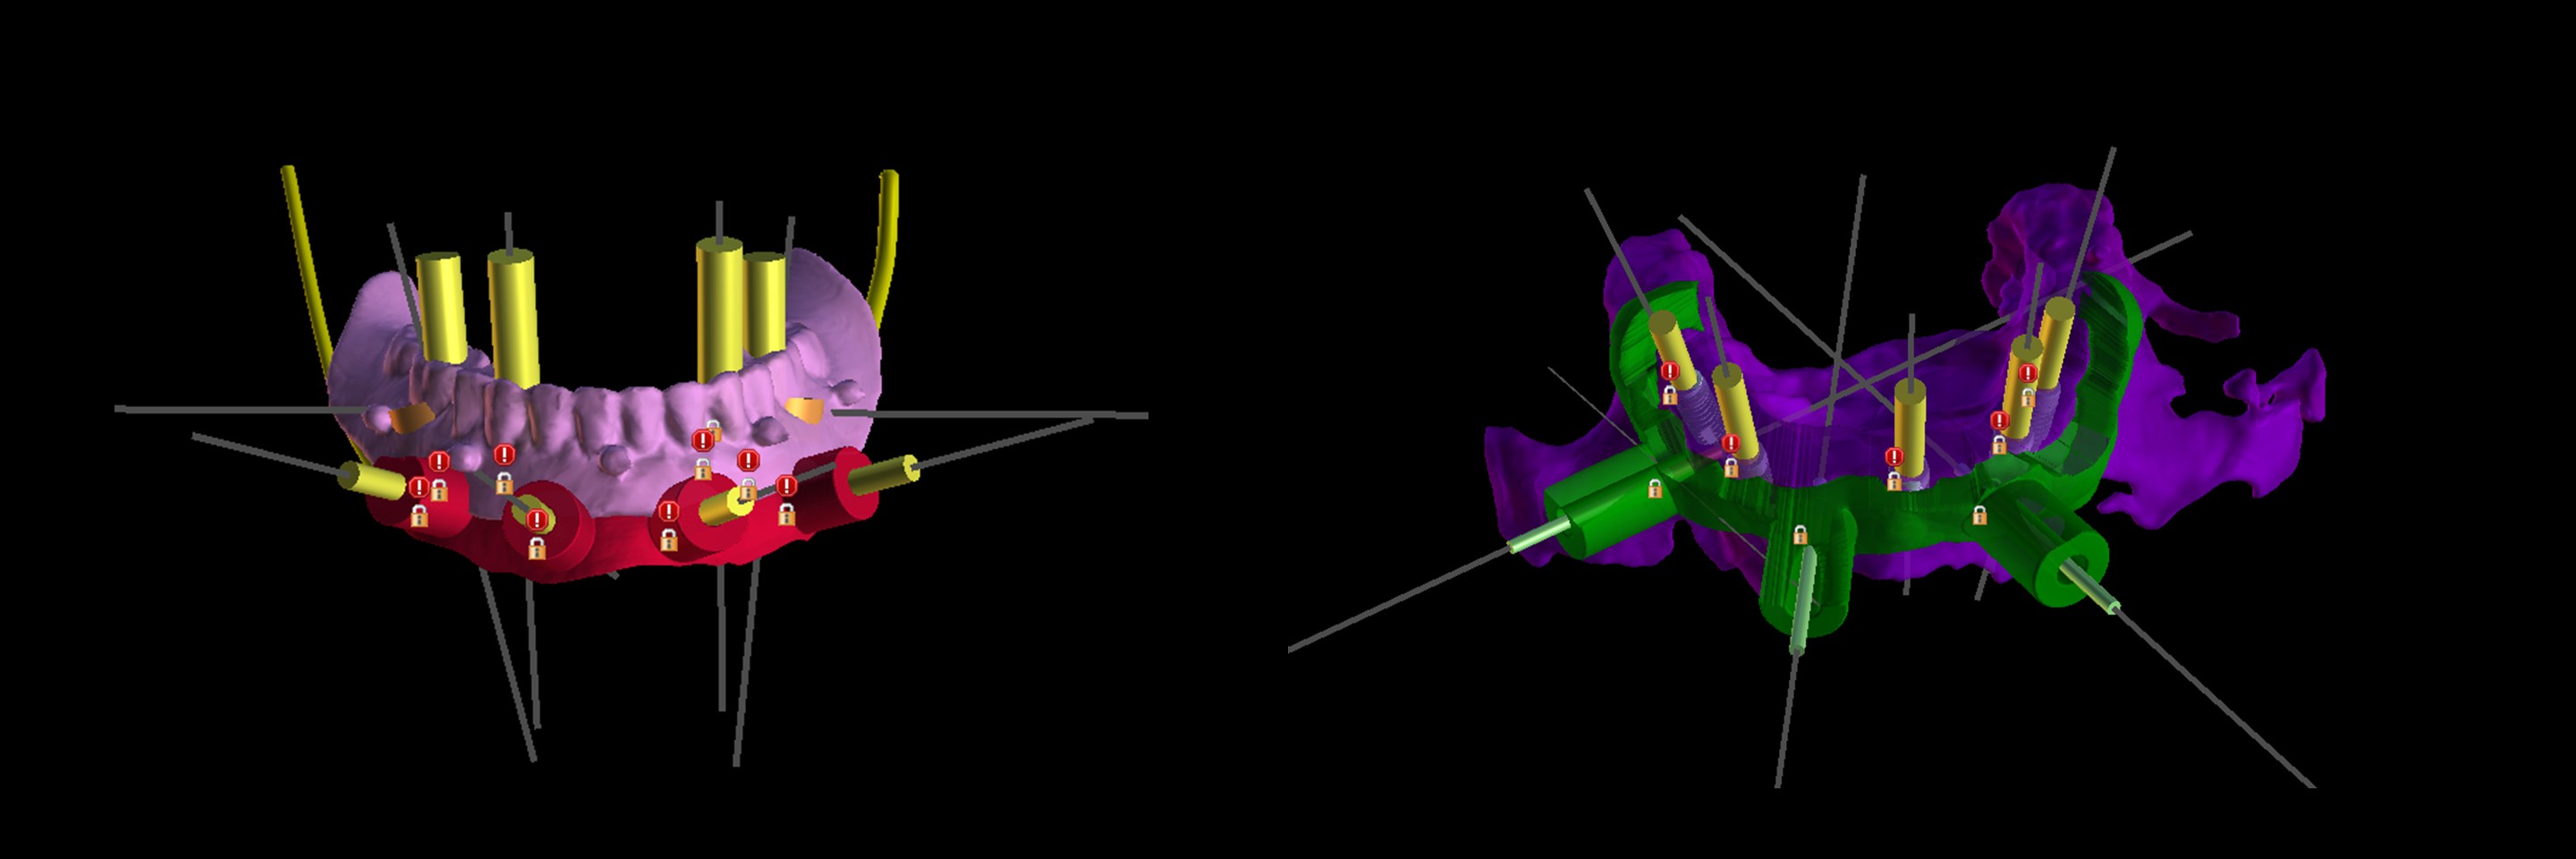

Director’s Clinical Cases

Director’s Clinical Cases